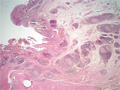

- (5)Intestinal tuberculosis

appearance: The ileocecum demonstrates annular ulcer and scar formation in this case of tuberculosis.